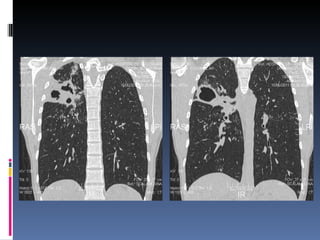

Estudios por imagen:   ECOGRAFIA ABDOMINAL Y TOCOGINECOLOGICA : sin alteraciones TAC  DE  TÓRAX c/c :

TAC de Tórax (13/06/11):

TAC de tórax: 15/06/11

TAC de Tórax(13/06/11):